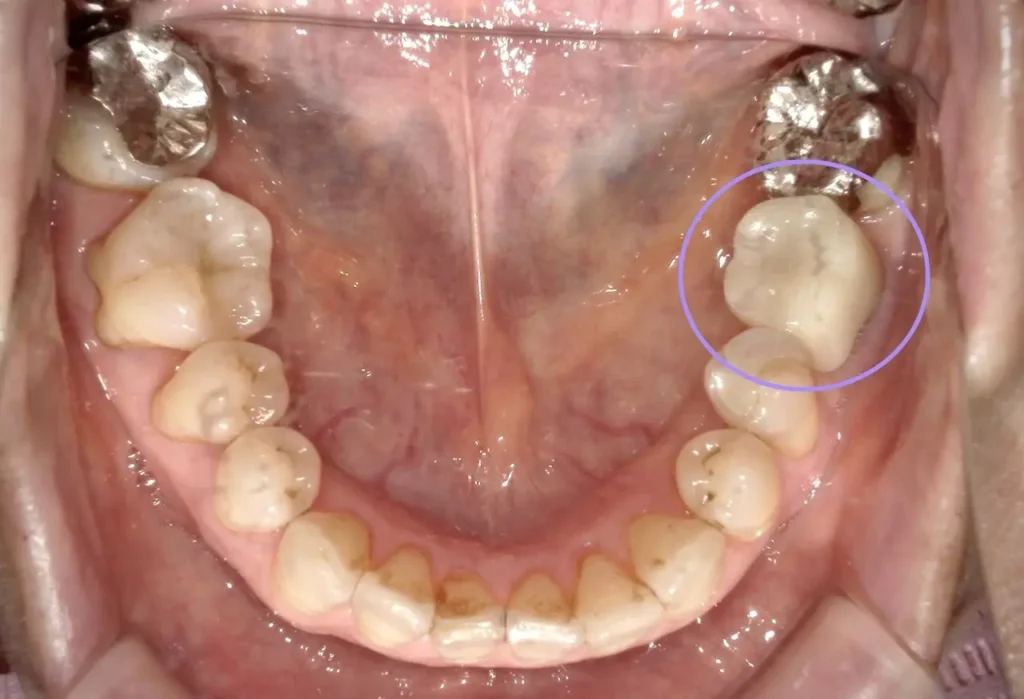

術中

長年の放置で土手の骨が吸収。

術後

移植直後は支える骨が少ないです。

術後3年経過

骨もしっかり増生してよく機能しています。